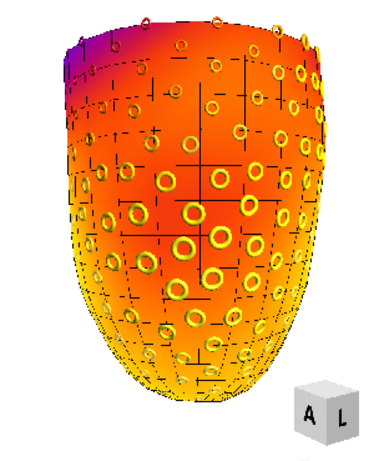

10.07.2010

4. Münsteraner MTRA Symposium

4. Münsteraner MTRA Symposium

10.07.2010

4. Münsteraner MTRA-Symposium

4. Münsteraner MTRA-Symposium